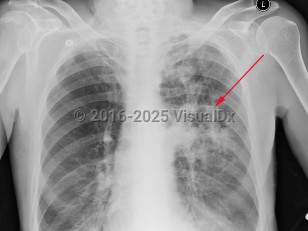

Pulmonary nocardiosis

Pulmonary disease can present as pneumonia, a lung abscess, a cavitary lesion, or an empyema that can extend to the chest wall. Pulmonary infections are usually subacute and chronic, manifesting with a variety of radiologic manifestations. An acute fulminant pneumonia may occur. Pulmonary nocardiosis is frequently difficult to diagnose and diagnosis is often delayed. Symptoms include purulent cough, pleuritic chest pain, and fever. Hemoptysis occasionally occurs.